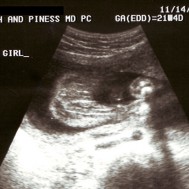

Mam: Pregnant 23 weeks (Baby 21 weeks)

Gallery